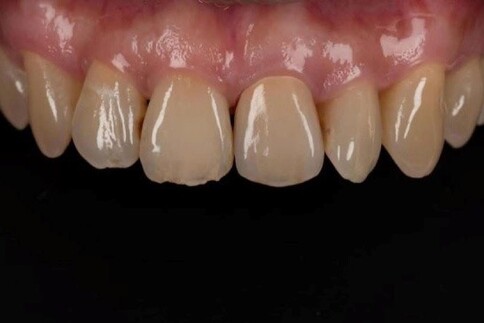

✨ 三、 四至六顆:微笑曲線重塑

Case 7:外突內收打造理想笑線,提亮色階。